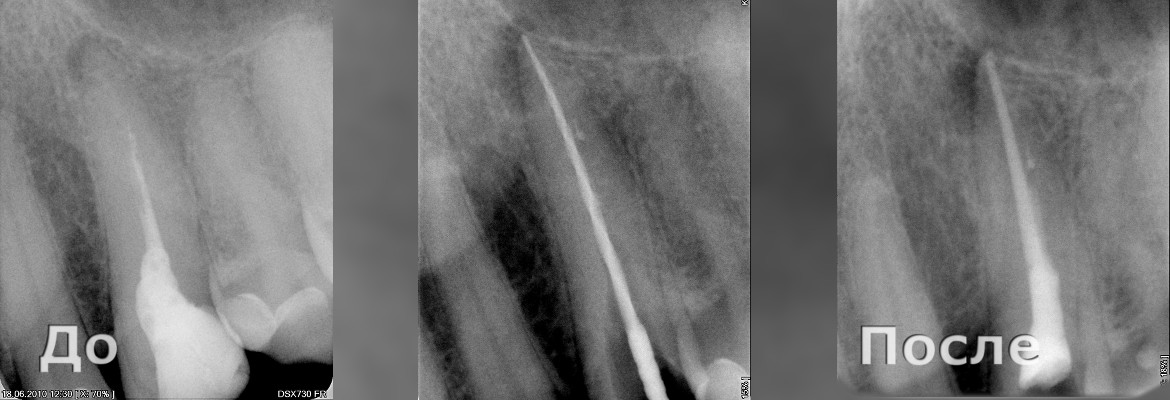

Перепломбировка канала